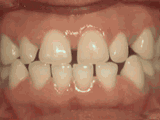

Spacing of teeth

Patient was bothered by the spaces between his teeth. Braces closed the spaces and gave him an ideal bite in 24 months. Special glued-in retainers help keep the spaces closed.